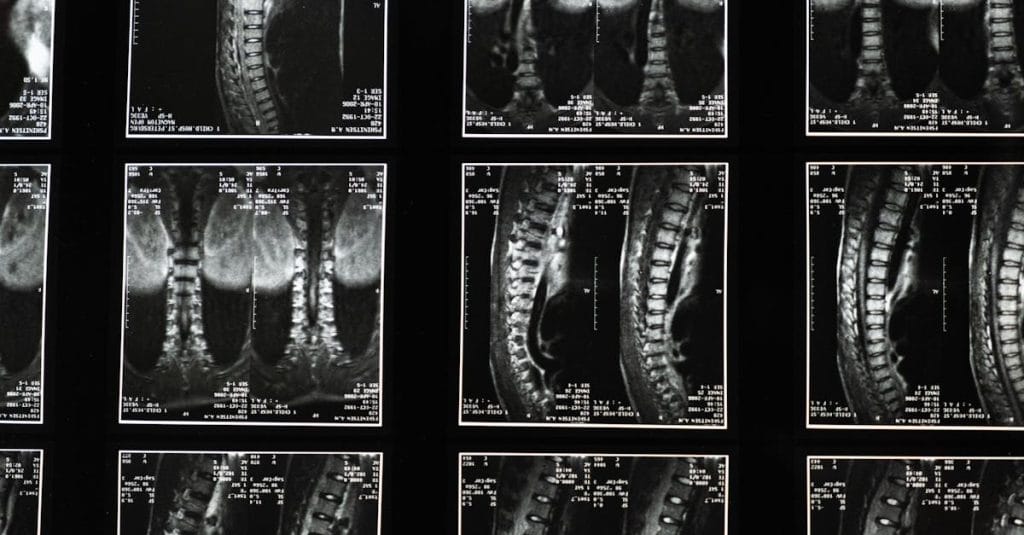

Quels examens sont nécessaires avant de commencer un traitement de décompression pour la sciatique?

Une IRM ou une radiographie est généralement recommandée pour évaluer l’état de la colonne vertébrale.